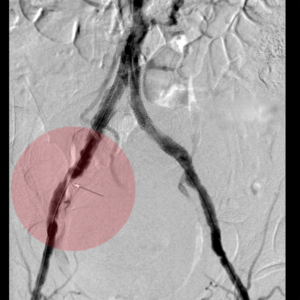

5. Thrombektomie – mechanische Entfernung von Blutgerinnseln

Wenn ein Gefäß durch Blutgerinnsel verschlossen ist, kann man den Verschluss mechanisch wiedereröffnen, indem man die Ablagerungen über spezielle Katheter absaugt. Dazu stehen uns Kathetersysteme, die mit Vakuum arbeiten bzw. zusätzlich die Gerinnsel vor dem Absaugen mit Hilfe von Wasserstrahlen oder Rotation der Katheterspitze zerkleinern, zur Verfügung.